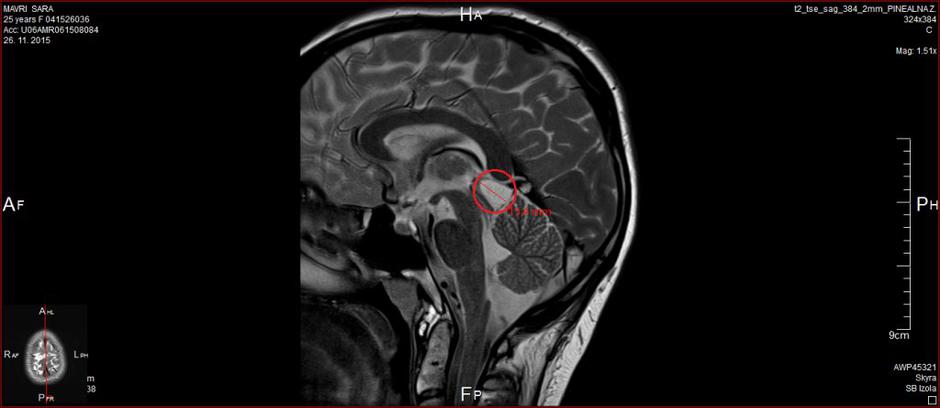

Nato je zamenjela osebno zdravnico. Pojasnjuje, da jo je nova zdravnica jemala bolj resno in jo poslala na vse potrebne preiskave, med drugim tudi na MR glave, ki je bil odločilnega pomena za odkritje tvorbe, ki ji je ves čas povzročala številne težave. MR je odkril benigni tumor na pinealni žlezi v glavi dolg 16 milimetrov in širok 10 milimetrov.

Sara slika glave | Avtor: Andreja Cilenšek Andreja Cilenšek